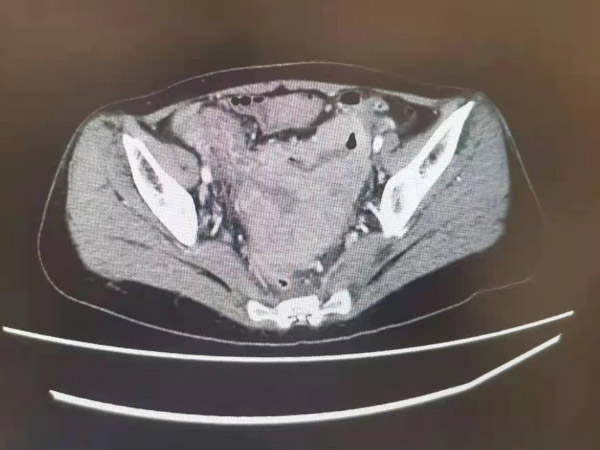

2020年9月,57歲的患者李阿姨因為腹脹、排便困難到我院就診,經(jīng)完善相關(guān)檢查后,發(fā)現(xiàn)李阿姨盆腔內(nèi)有一顆(7.5cmx11.1cmx8.6cm)腫瘤,相當(dāng)于一個鉛球大小。由于腫物太大,占滿了盆腔,廣泛侵犯子宮后下壁、左側(cè)盆壁、右側(cè)盆壁,暫時無法手術(shù)治療,患者得知自己的病情,惴惴不安的心跌到了谷底。“阿姨,您放心,我們會盡100%的努力去解決您的問題!”我院胃腸外科負(fù)責(zé)人賀孝文不停為患者打氣,這猶如一顆定心丸,讓李阿姨恢復(fù)了戰(zhàn)勝病魔的信心。

經(jīng)過系統(tǒng)治療,醫(yī)患雙方的堅持和不懈努力,轉(zhuǎn)化治療有效,盆腔腫物不斷縮小,2021年7月,MDT團隊通過對患者復(fù)查CT結(jié)果慎重、嚴(yán)格評估,腫物已由不可切除轉(zhuǎn)化為可切除。7月20日,胃腸外科手術(shù)團隊為李阿姨實施了腹腔鏡下直腸根治性切除術(shù),徹底將盆腔內(nèi)的“定時炸彈”解除了。